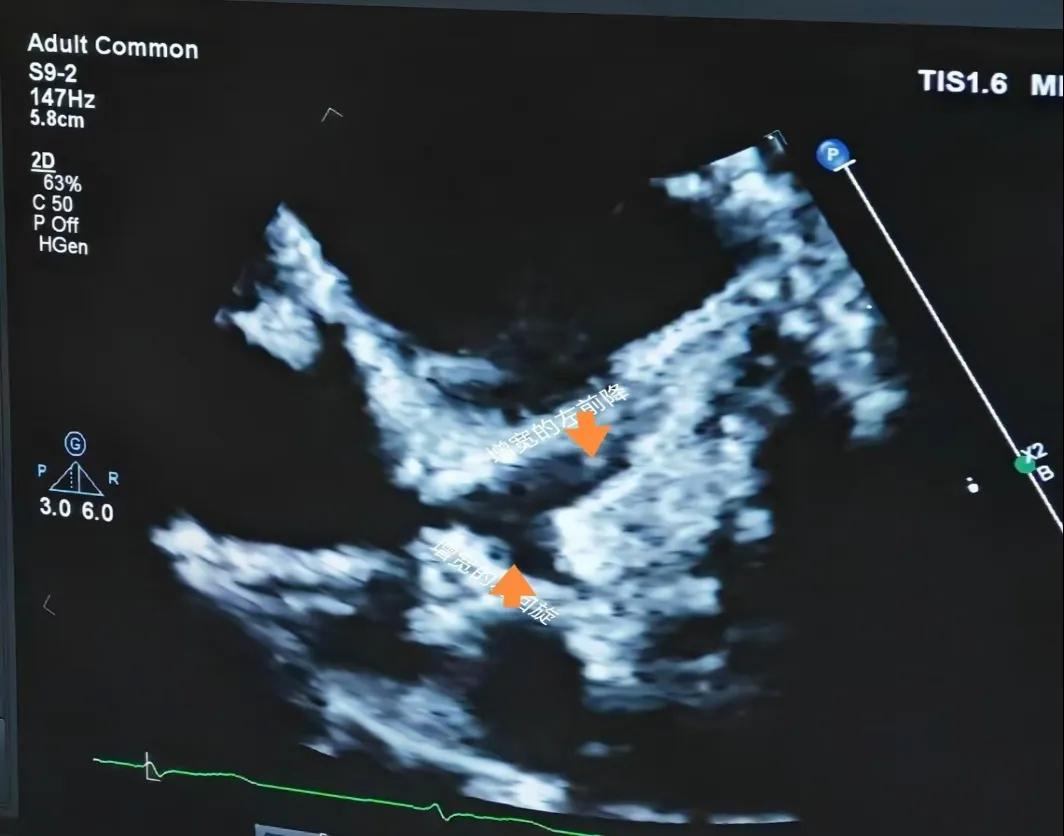

(川崎病患兒:增寬的左前降支和左回旋支)